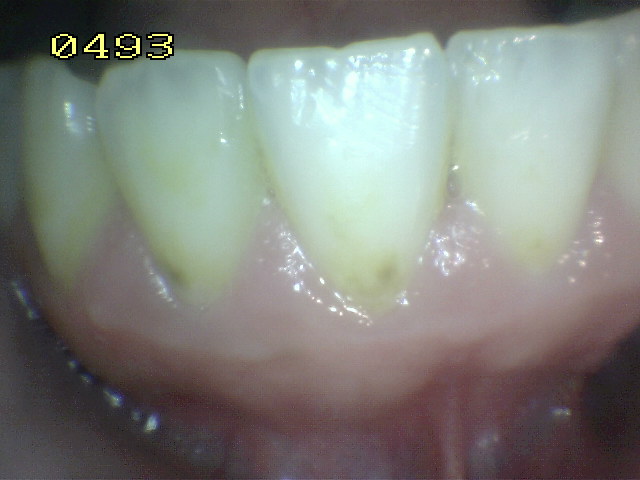

- Hacer examen visual de la superficie húmeda:

- Inicie desde el cuadrante superior derecho del

paciente

- Prosiga con la orientación de las manecillas del

reloj

- Inicialmente el examen visual se realiza con las

superficies húmedas.